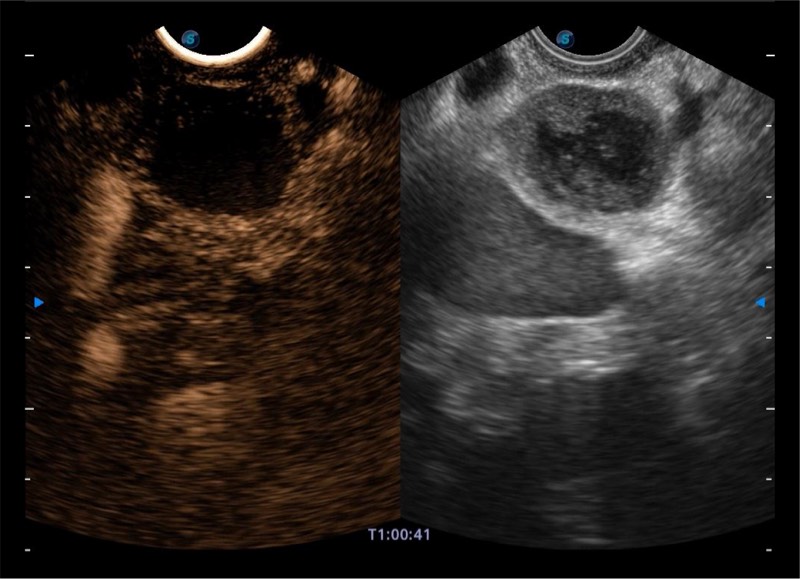

• 搭载百万级CMOS成像技术

• 及自主研发凸阵换能器,

• 可呈现优质的内镜和超声画面

基于二十年的超声技术积累,新葡的京集团8814检测站提供了最新一代的独立超声主机,在提供高质量图像的同时满足多学科使用。具备常见多普勒技术并提供弹性成像、声学造影等高端影像技术。新一代传感器具有更强的抗干扰能力并减少图像伪影。